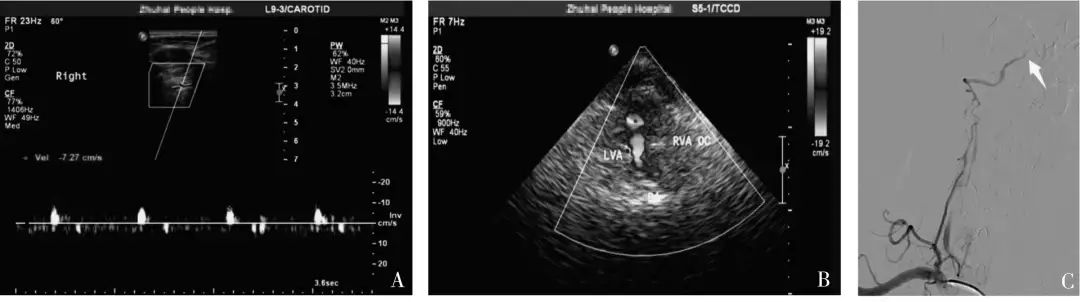

2019年9月,暨南大學(xué)附屬珠海醫(yī)院報道了一項研究[1],經(jīng)由CTA或DSA結(jié)果證實為單側(cè)椎動脈顱內(nèi)段閉塞患者40 例,由未規(guī)范培訓(xùn)組醫(yī)師和規(guī)范培訓(xùn)組醫(yī)師分別進行血管超聲檢查,將兩組超聲診斷結(jié)果與金標準結(jié)果進行比較,并對兩組不同資歷醫(yī)師進行診斷一致性分析。

結(jié)果:規(guī)范培訓(xùn)組診斷椎動脈顱內(nèi)段閉塞的敏感度及符合率(均為95%)明顯高于未規(guī)范培訓(xùn)組(均為75%),不同資歷的超聲醫(yī)師對于椎動脈顱內(nèi)段閉塞的一致性檢驗結(jié)果Kappa 值為0.273,診斷一致性較差。

中國腦卒中血管超聲檢查指導(dǎo)規(guī)范[2]指出:若椎動脈閉塞于小腦后下動脈分支之前,椎動脈顱外段可探及低速單峰型(無舒張期血流信號);若椎動脈閉塞于小腦后下動脈之后,椎動脈顱外段可探及低速高阻型(舒張期流速低平)血流信號。

本研究中,未規(guī)范培訓(xùn)組椎動脈椎間隙段頻譜形態(tài)呈“高阻型”10 例中,全部診斷為椎動脈發(fā)育不良,“單峰型”30 例全部診斷為顱內(nèi)段閉塞。

當(dāng)椎動脈椎間隙段內(nèi)徑≤2.5 mm,頻譜形態(tài)呈低速高阻型改變時,既有可能是椎動脈發(fā)育不良,也有可能是椎動脈顱內(nèi)段閉塞,此時應(yīng)聯(lián)合TCCS(或TCD) 檢查,直觀地從枕窗觀察雙側(cè)椎動脈顱內(nèi)段的血流充盈情況。